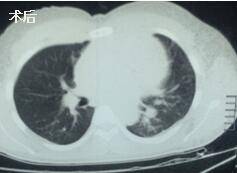

當(dāng)看到病人癥狀緩解,復(fù)查胸部CT幾近完美,我們那種自豪感油然而生。偶爾去治愈,常常去幫助,總是去安慰,我們深知,小伙子的人生之路并不長(zhǎng),只能深深祈禱他在我們的治療下能走得更遠(yuǎn)一些,能把剩下的日子走的更充實(shí)一些。而我們?cè)谀軌驇椭说臅r(shí)候,別一味地去安慰,永不言棄,是我們這一群胸外人堅(jiān)貞的信念。